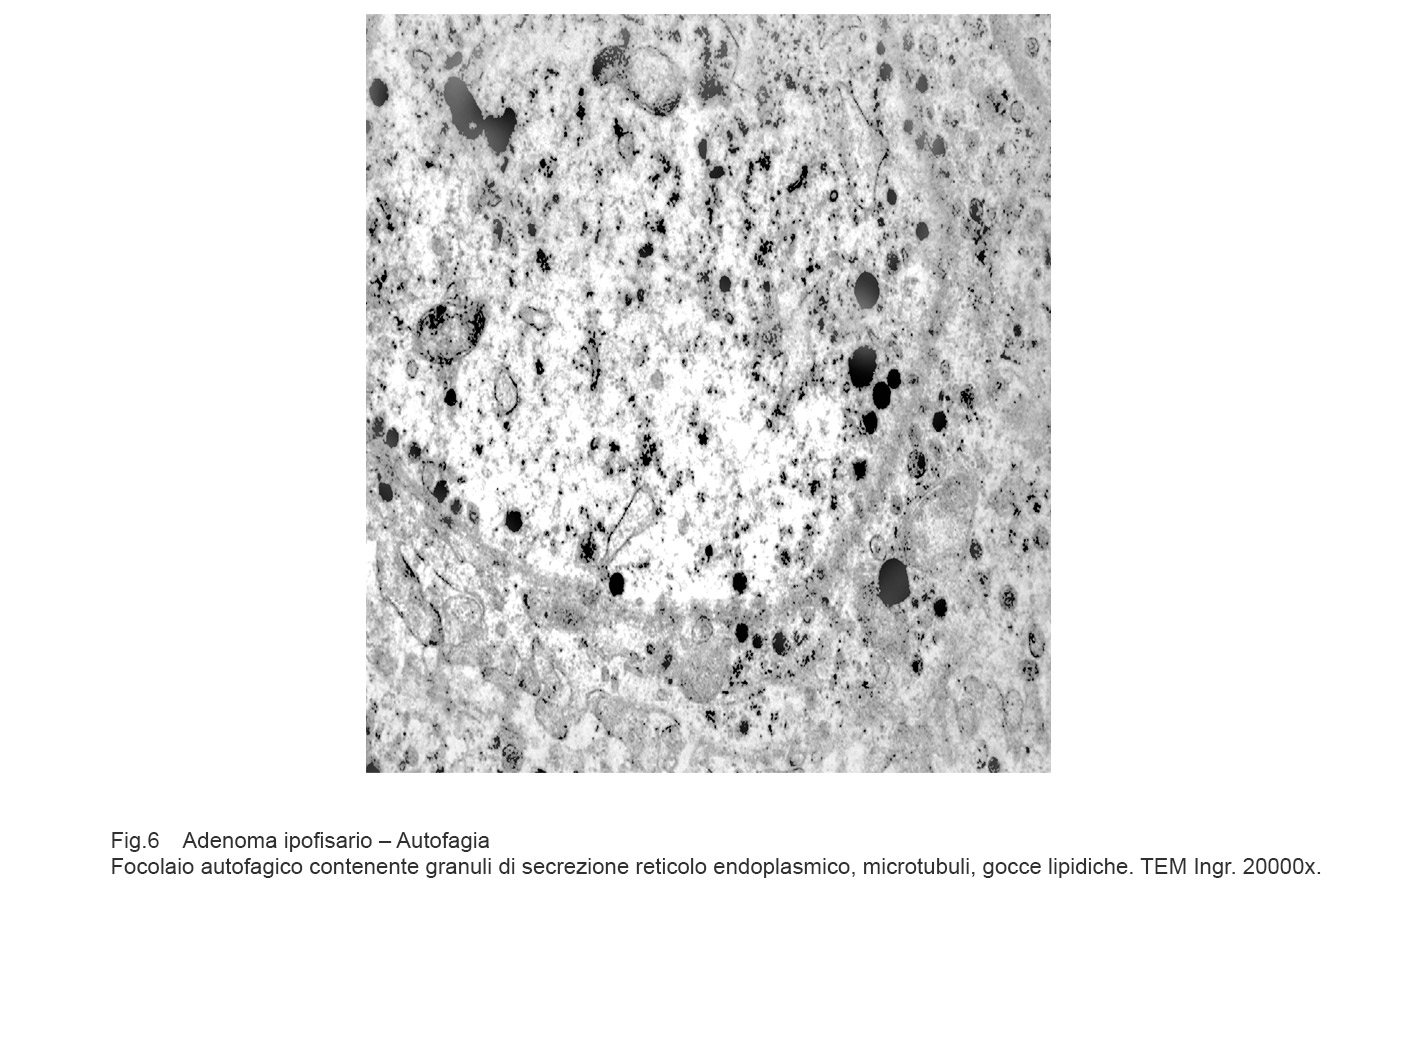

I focolai di autofagia sono di grandezza diversa e sono caratterizzati da una membrana a doppio strato e da contenuti rappresentati da frammenti di reticolo endoplasmico, da mitocondri in varie fasi di degradazione, da gocce lipidiche, da granuli di secrezione, da ribosomi, da microtubuli e da materiale amorfo.

Gli aspetti ultrastrutturali qui riscontrati sono conseguenti non solo alla tipologia delle substrutture inglobate ma anche alla fase di degradazione nella quale cade l’osservazione microscopica. E’ possibile documentare la esistenza di un focolaio di autofagia inglobante mitocondri, reticolo endoplasmico, microtubuli e citosol ancora in discreto stato di conservazione.

Fig.6